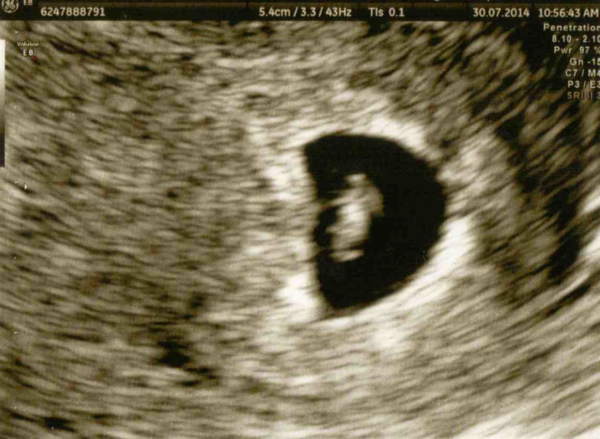

Here's my scan pic for those who asked Grin

smoke i cant see your scan photo on the app but glad little bean is ok in there Grin

Oh smoke I can see your little bean - how exciting!!!!

Thanks Zebra! Couldn't believe the little heartbeat either! So exciting! Grin

smoke what a beautiful scan!!